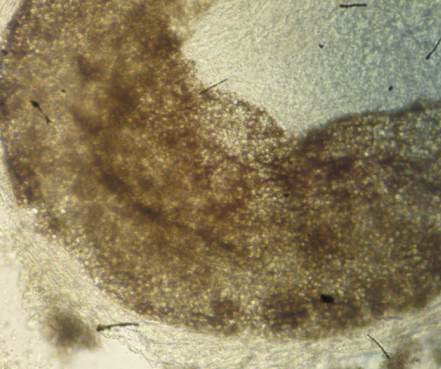

Para la confirmación, se les practicó microcultivo, prueba de hidrólisis de la urea y prueba de perforación del cabello. A los cinco días de esporulación en el microcultivo, se observaron las características micromorfológicas de la conidiogénesis: hifas anchas irregulares, ramificadas, con numerosos tabiques, microconidios de varios tamaños y clamidosporas terminales (figura 6).

En el examen físico, se encontraron 32 niños con lesiones alopécicas, descamativas, no inflamatorias, en punto negro. Dos de ellos presentaban lesiones en el tórax, indicativas de pitiriasis versicolor. La observación microscópica de las muestras de escamas de estas lesiones torácicas resultó positiva para tinea capitis. Las 32 muestras de cabellos se analizaron mediante microscopía, previo tratamiento con preparación de hidróxido de potasio (KOH al 40 %) y, en el 78 % (26/32), se detectó parasitismo pilar de tipo endotrix tricofítico (figura 4). De estos, cinco cultivos fueron negativos, mientras que, en los restantes, se aisló e identificó T. tonsurans (63 %; 21/32).

En el presente estudio se pudo observar, por sus características, que los 32 niños presentaban un cuadro clínico sugestivo de tinea capitis seca. En el examen directo, por microscopía, se detectó parasitismo pilar de tipo endotrix tricofítico en el 78 % (25/32) de los casos. Esto indica que solo en el interior del cabello se encontraron artroconidios del hongo, con un diámetro superior a 8 µm, sin destrucción de la cutícula y congruente con el tipo de parasitismo pilar que desarrolla T. tonsurans18-20.